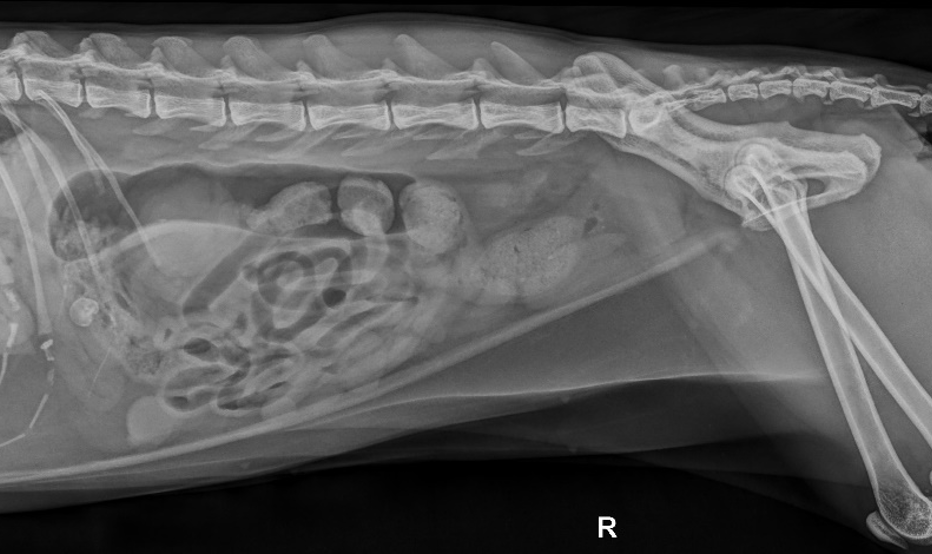

Eine zentrale Rolle spielt die bildgebende Diagnostik. Das Abdomenröntgen sollte immer in zwei Ebenen durchgeführt werden, um Beckenengstände oder alte Traumata sicher beurteilen zu können. Zur Diagnostik eines Megakolons wird der Kolondurchmesser mit der Länge des Wirbelkörpers von L7 verglichen. Ein Durchmesser von mehr als dem 1,5-fachen der L7-Länge gilt als zuverlässiger Hinweis auf ein Megakolon. Ultraschall kann strukturelle Veränderungen wie Entzündungen oder Neoplasien darstellen. Eine Kolonoskopie ist selten erforderlich, kann aber bei Strikturen oder intraluminalen Massen hilfreich sein. Bei neurologischen Auffälligkeiten können weiterführende Untersuchungen wie CT oder MRT notwendig werden.